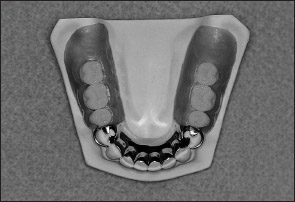

Another method for categorizing removable partial dentures relates to the manner of their support. A partial denture that receives support from natural teeth at each end of the edentulous space or spaces is a tooth-supported removable partial denture (Fig 1-6). Although the denture base contacts the adjacent soft tissues, the prosthesis does not receive significant vertical support from the residual ridge.

Fig 1-6 A tooth-supported removable partial denture.